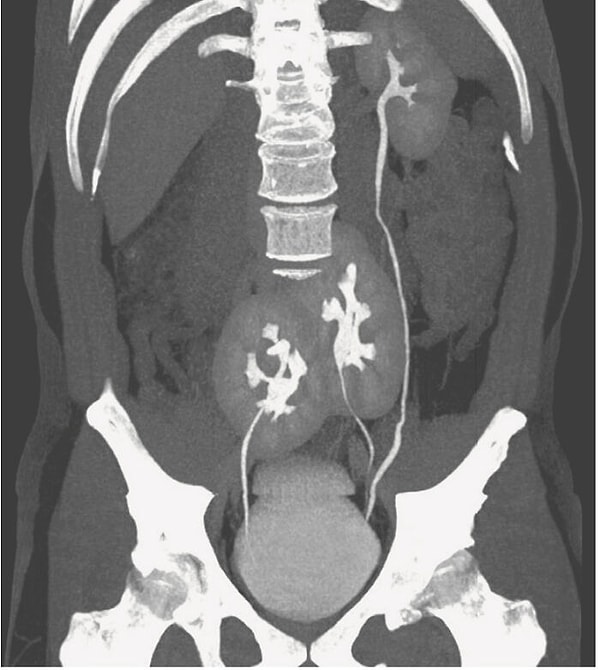

19. У мужчины обнаружены три почки! - Медицинский случай